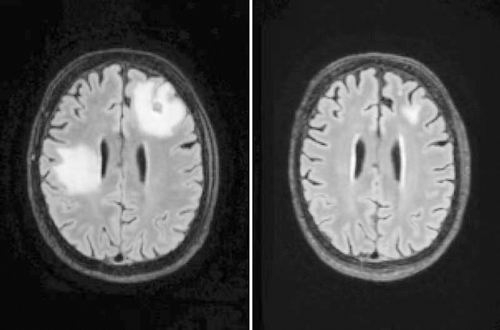

MRI显示,一名脑部感染巴氏阿米巴原虫的男子在接受实验药物治疗前(左)后炎症(白色部分)存在显著差异。

Spottiswoode联系到了DeRisi,但对方表示他们还没有机会使用硝羟喹啉在实际感染者身上进行检验,且该药物没有获得美国食品药品监督管理局的批准。最终,在多方协调下,美国亚虹医药公司为UCSF医疗中心无偿提供了数百粒药片,仅用硝羟喹啉治疗1周后,患者的病变即缩小。随访MRI也显示病情正持续改善,患者现已出院在家中接受后续治疗。近期,第二名患者也开始服用该药物,初步检测结果同样令人鼓舞。(徐锐)